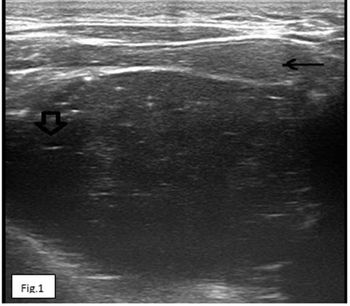

An 18-year-old boy with complaints of swelling in floor of mouth since childhood and difficulty with movement of tongue. On physical examination, sublingual large swelling was noted. Overlying surface was reddish, however no signs for active inflammation seen. Ultrasound, contrast enhanced CT scan and MRI were done.